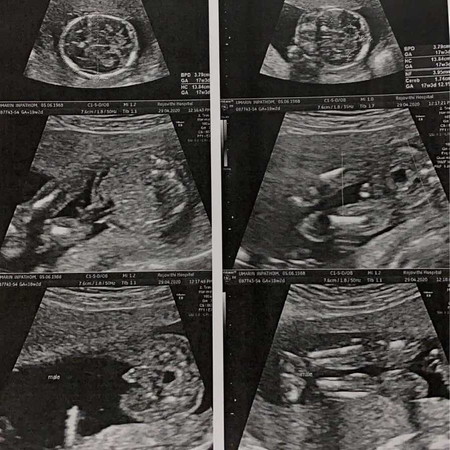

สวัสดีคุณแม่ทุกคน. เราเป็นแม่มือใหม่ ท้องแรก เราเป็นโรคลิ้นหัวใจรั่ว หมอบอกว่าเสี่ยงมาก อันตรายทั้งแม่และลูก มากกว่า 50% แต่เราก็ยืนยันจะเอาเด็กไว้ เพราะอยากมีมากๆ ตอนนี้ 18+2w. แล้ว หมอบอกได้ลูกชาย แข็งแรงดี เลือดดี มือเท้าดีหมดโคตรดีใจเลย เราจะต้องสู้จนวินาทีสุดท้าย ทั้งพ่อแม่ แฟน พี่ๆ น้าๆ ไปบนบานไว้ให้เราและลูกปลอดภัย. เราก็ขอให้เราและลูกปลอดภัยเช่นกัน เป็นกำลังใจให้ด้วยนะคะ❤️❤️